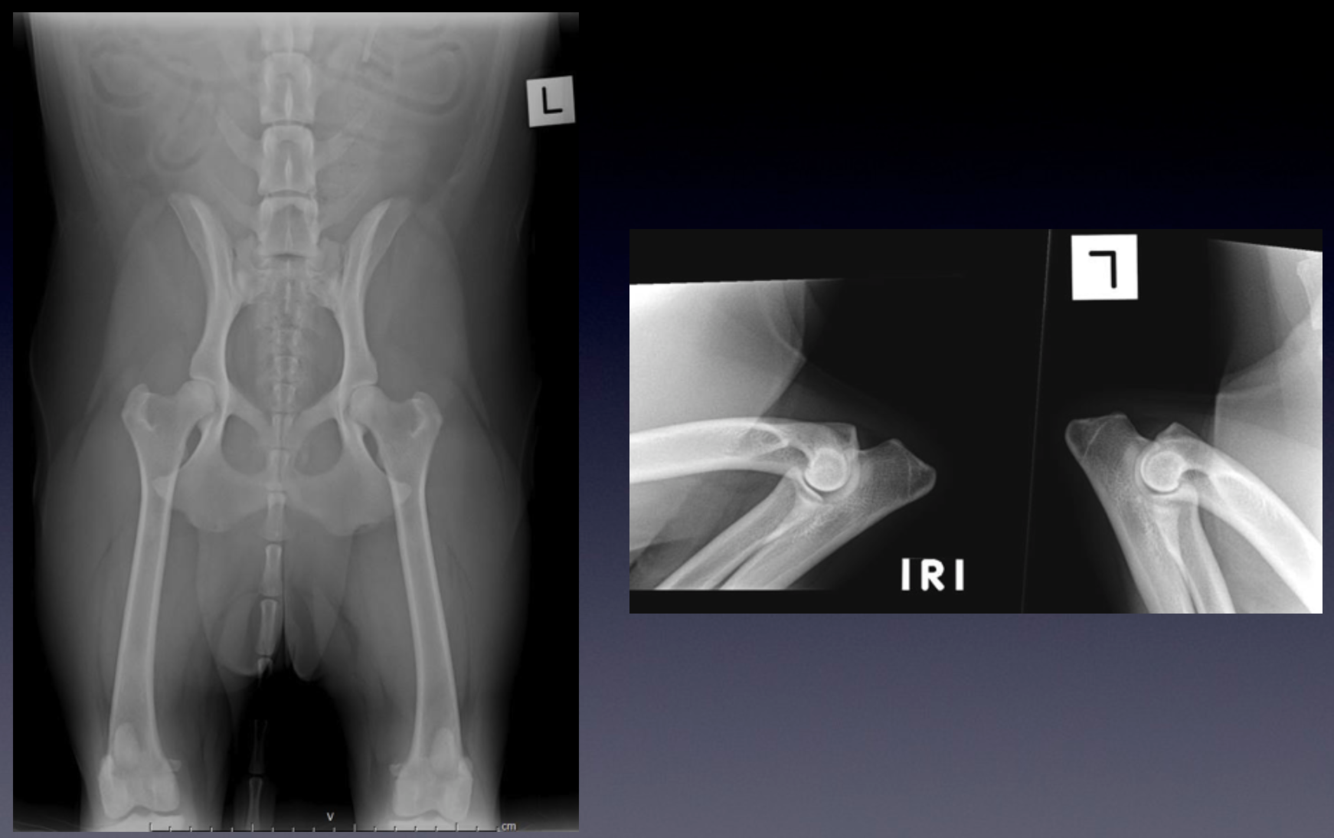

Patient number 242727 - Normal Hip and Elbow Screening Radiographs

These radiographs were taken to screen the patient for the presence of hip and elbow dysplasia.

VIEW?

Notice:

1.

The collimated field includes the entire pelvis and femoral condyles/stifle joints

2.

The symmetry of the pelvis, with similar appearance to the iliac wings and symmetric size of the obturator foramina

3.

The femurs are parallel

4.

The patellas are superimposed over the femoral trochlea.

5.

These radiographs are normal, but when evaluating hip radiographs:

note the congruence of the coxofemoral joints

look for evidence of osteoarthritis

6.

These factors are considered when allocating a final hip ‘score’.

The elbows are taken as mediolateral projections with the elbows in full flexion.

The medial and lateral portions of the humeral condyle are superimposed, forming parallel curved surfaces.

When the elbow is in full flexion, the anconeal process is readily visible.

These elbows are normal, but in a patient with elbow dysplasia there will be early signs of arthritis

osteophyes on the anconeal process

sclerosis of the ulna trochlea notch

In more advanced cases of arthritis, osteophytes are seen associated with all aspects of the elbow joint

The pelvis view is a ‘Ventrodorsal, hip extended’ projection.